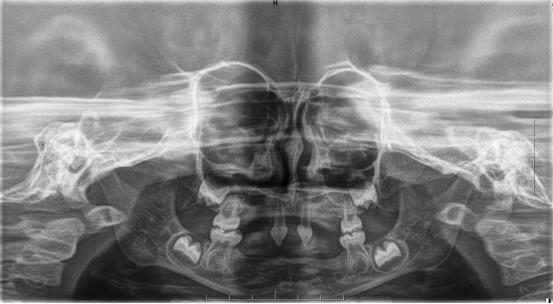

近年来,小艾电竞官方网站(后文简称小艾电竞 )在临床诊疗方面每年均有多个技术创新或突破。期间,副院长、口腔修复种植科主任医师王永曾带领团队完成多名外胚层发育不全患儿的可摘局部义齿及全口义齿修复,222日,更是为一位4岁患儿完成了罕见外胚层发育不全可摘局部义齿修复该患儿为目前口腔医院完成修复治疗年龄最小的患者

患者4岁,乳牙未正常萌出,上颌仅4下颌仅2颗乳牙,不能正常咀嚼,于2022年底在外地就诊多次无法修复,专程到口腔医院就诊。在后疫情时期,患者经王永门诊诊治后商讨出诊疗方案医院细心安排,于222由王永带领谭雯珈、姜炜鹏等医师,使用修复、正畸、修复工艺等多项技术,顺利完成了大面积乳牙缺失修复患儿现场进食效果良好,家长及患儿十分满意。

因其口腔表征为先天缺牙甚至无牙颌,且缺牙患儿口内余留牙往往表现为锥形牙、釉质发育不良、牙槽嵴发育不良等,可严重影响患儿的咀嚼功能及面部软硬组织生长发育。